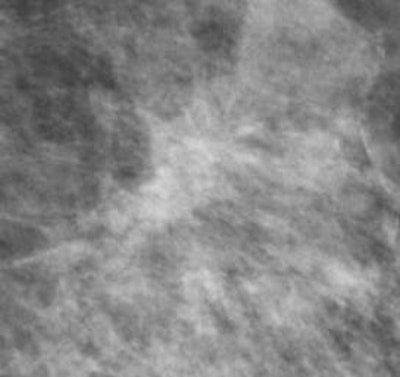

With tomosynthesis, low-dose images are obtained over a limited arc, and the projections are mathematically reconstructed into a series of sections with the hope that specificity and sensitivity will be improved. Initial work using tomosynthesis as an add-on to conventional 2D mammography suggested the potential for substantial improvements in specificity, the authors noted. They compared the diagnostic accuracy of 2D digital mammography with that of two-view (mediolateral and craniocaudal) and single-view (mediolateral oblique) tomosynthesis in an observer study involving two institutions: Cambridge and Capio St Göran's Hospital in Stockholm.

For diagnostic accuracy, 2D mammography performed significantly worse than two-view tomosynthesis (average area under receiver operating characteristic curve [AUC] = 0.772 for 2D, AUC = 0.851 for tomosynthesis; p = 0.021). The researchers found significant differences for masses and microcalcification (p = 0.037 and 0.049, respectively). The difference in AUC between the two modalities was significant only for the five readers with the least amount of experience (p = 0.03 versus p = 0.25 for readers with 10 or more years of experience). No significant difference was seen in reader performance when 2D mammography was compared with single-view tomosynthesis.

"The role of tomosynthesis is still being clarified," Wallis wrote. "It has the potential to be an additional tool for the workup of screening-detected and clinical abnormalities."